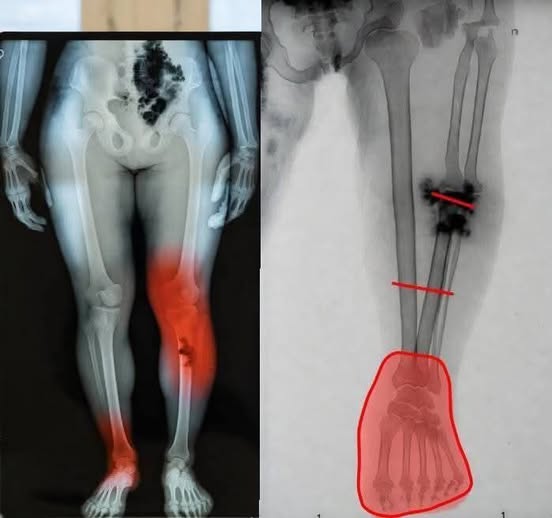

The X-ray images in the post appear to show localized injury or possible trauma to the lower leg and foot. Radiologists note that such findings are typically associated with fractures, infections, vascular issues, or other unrelated medical conditions — not vaccination.